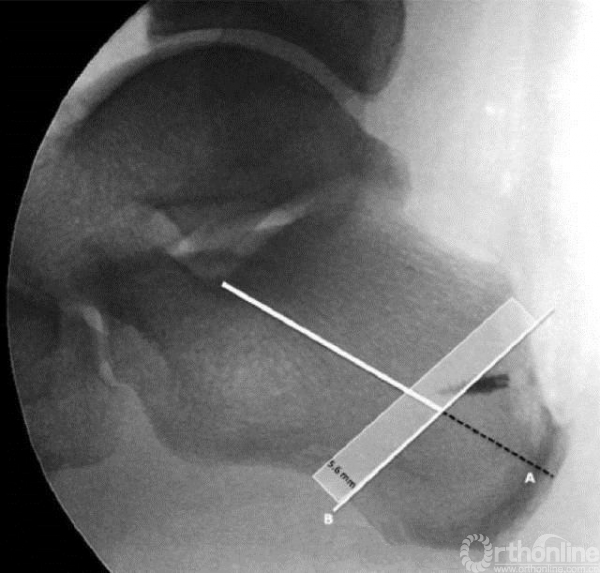

如患者曾行Haglund畸形骨赘清理术,跟骨后上结节已切除,很难用以上方法定位标志线,需按以下方法定位A线(标志线):

A线是自Gissane角向跟骨结节最后方划的一条线,

B线是平行于截骨方向的直线,它位于A线从Gissane角向远端走行的60%处。

安全区为B线近端5.6mm的区域内(图中阴影区)。